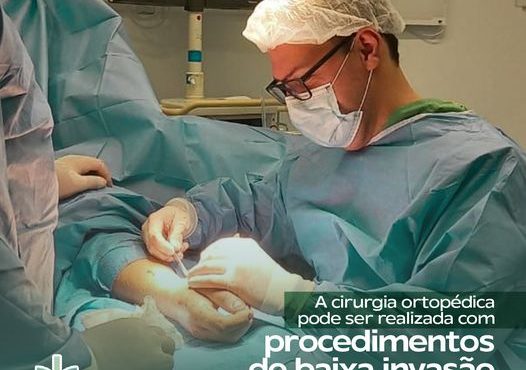

A cirurgia ortopédica pode ser realizada com procedimentos de baixa invasão.

Você tinha conhecimento de que o estresse […]